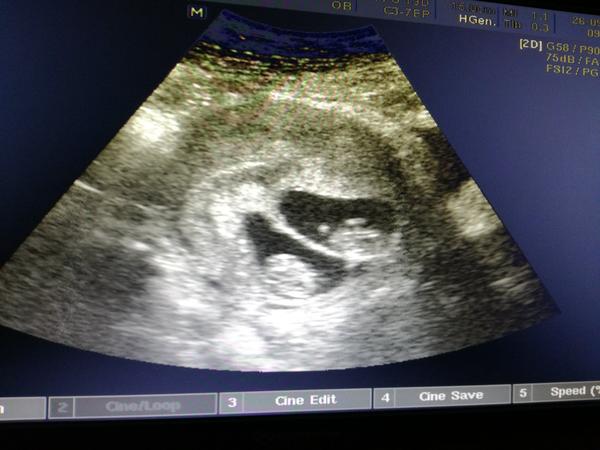

@fialka444 6+6 🙂 plod už vidět, 3mm, srdeční akce přítomna